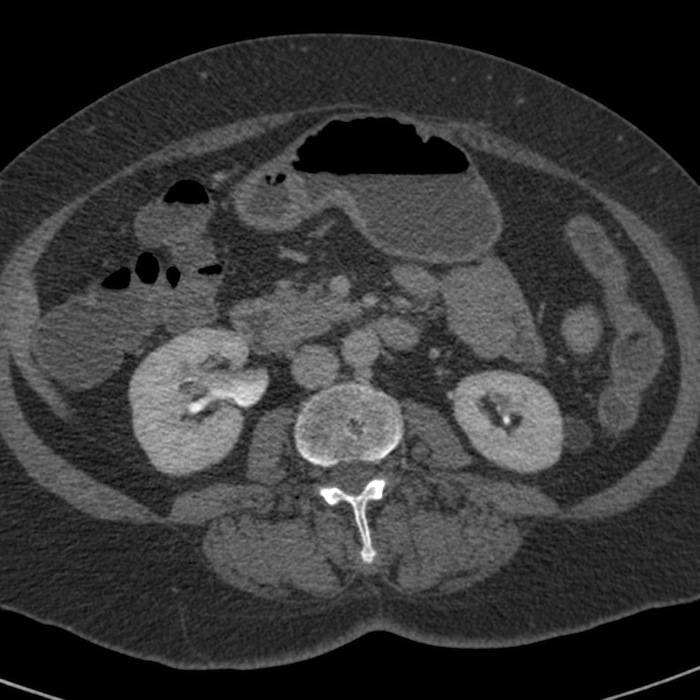

КТ ретроперитонеального фиброза: Изображения и диагностика